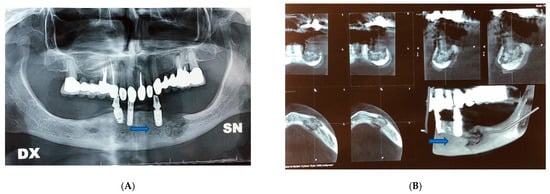

Surgery was performed under general anesthesia. We proceeded to the superficial removal of damaged tissues in the site of the osteonecrosis outbreak to avoid extension of the necrosis and to enhance healing abilities. We eliminated all the necrotic tissue, saving healthy tissue at the excision border to preserve as much as possible mandibular contour aesthetic and function. To stabilize the bone segment, an epi-mucosal fixation was performed using SMART Lock screws and plates without elevation of the mucoperiosteal flap, therefore avoiding any new bone necrosis risk (Figure 1C).

Figure 1.

Patient 1. (A) Pre-operative CT scan image showed lithic area in the mandibular horizontal branches, which appeared subverted and fractured on the left side. (B) Pre-operative panoramic X-ray image of the dental branch revealed lithic area. (C) Epi-mucosal fixation performed using SMART Lock screws and plates without elevating the mucoperiosteal flap. (D) Post-operative panoramic X-ray image of the dental branch. (E) Post-operative CT scan image. (F) Post-operative CT scan 3D reconstruction.

The self-locking screws and plate were inserted before the necrotic bone area resection or sequestrectomy by epi-mucosa plate modelling, positioning and fixing with trans mucosa screw insertion. No need for mucosa incision or periosteal elevation was required at this step of the procedure; the self-locking screws and plate acted as a rigid external fixation system.

For case one, patient physical examination showed no obvious swelling of the face. CT examination showed a lithic area in the mandibular horizontal branches, which appeared subverted and fractured on the left side (Figure 1A). A panoramic X-ray image of the dental arches has revealed the same characteristics (Figure 1B). The alteration was bilateral but particularly accentuated on the left. An additional bone lysis area was also appreciated at the D8 body level. A pathological fracture with radiographic evidence of osteolysis extending to the inferior border of the mandible was compatible with a diagnosis of stage 3 MRONJ caused by the continuous use of denosumab for three years (administration of 1 vial subcutaneous every six months). Additionally, fistulas were present at the lower border of the mandible.